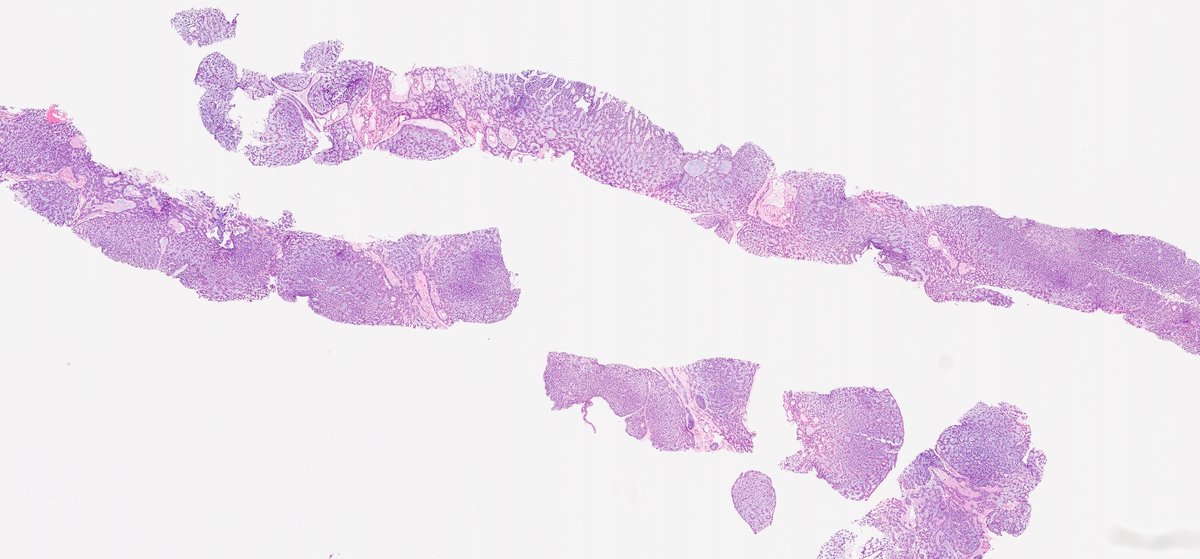

CC357. Long-standing hemopericardium. We talk a lot about molecular biology and very little about cell biology. One of those peculiar cytologic findings with no histological counterpart, so far Barry McGinn Kalyani Bambal Lorand Kis Mark Ong